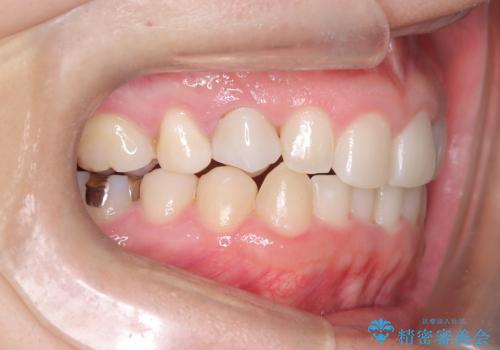

- 下の歯のがたつき(叢生)、真ん中(正中)が右にずれていることを主訴に来院されました。右上前から3番目の永久歯が埋まっている(埋伏)していることから正中は可能な限り合わせることをゴールとしてマウスピースでの矯正治療を選択しました。

今回の矯正治療では、透明なマウスピース型の装置インビザラインを使用しました。がたつきをとるため、安全性が確保できる範囲で歯と歯の間を少し削り必要なスペースを確保しました。